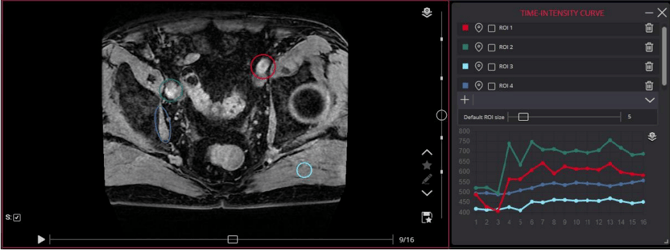

▫️ TIC Tool (Time-Intensity Curve)

Used in Dynamic Contrast-Enhanced (DCE) MRI to assess enhancement behaviour over time. Place regions of interest to generate a graph showing signal intensity changes during contrast phases.

A full preload of the dynamic series is required for this tool to function. Some dynamic MRI series may display in the viwer as separated series or instead of a large volume series stack of phases.